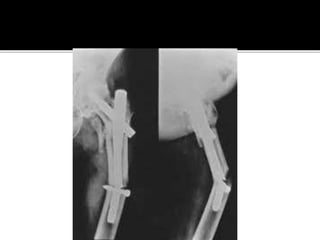

 Unstable pertrochanteric fractures may be fixed

either with locked extramedullary small-diameter

screw systems to avoid lateral wall fractures or with

the new intramedullary systems to avoid potential

mechanical complications of a broken lateral wall.

 Tip-apex distance and preservation of the

preoperative femoral neck-shaft angle are the key

technical factors for prevention of reoperation.